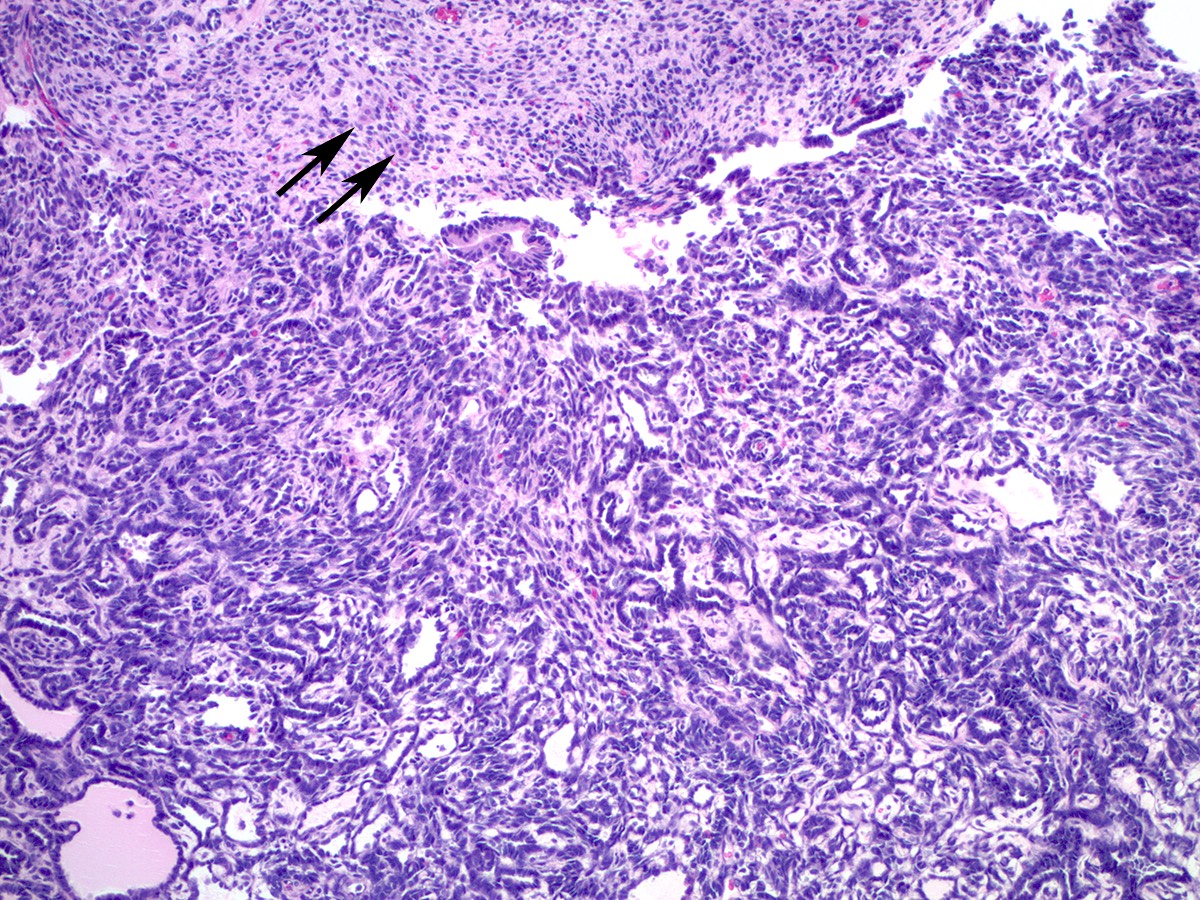

Microscopic (histologic) description

- Sertoli-Leydig cell tumor with heterologous elements

- Heterologous (epithelial or mesenchymal) elements may be seen in approximately 20% of moderately or poorly differentiated tumors and in retiform Sertoli-Leydig cell tumor (Am J Surg Pathol 1985;9:543)

- Most common heterologous element is mucinous (intestinal or gastric type) epithelium, which may be benign, borderline or malignant (Cancer 1982;50:2448)

- Carcinoid tumor (trabecular or goblet cell) has also been described arising from heterologous mucinous epithelial elements (Cancer 1982;50:2448)

- Heterologous mesenchymal (cartilage or skeletal muscle) elements are less common (Cancer 1982;50:2465)

- Rare focal hepatocyte differentiation has also been reported and may be associated with increased serum AFP (Hum Pathol 1999;30:611)

Microscopic (histologic) images